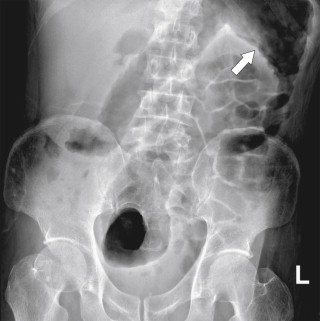

Plain radiography may demonstrate an ileus, sometimes confined to the left colon. As the disease progresses, bowel wall thickening develops ( Fig. 5-34 ) with a toxic megacolon if severe ( Fig. 5-35 ). BE is now rarely performed, but results demonstrate thickened folds and ulceration, either linear or with mucosal sloughing. Healing can lead to stricture formation ( Fig. 5-36 ). The findings are now usually made by CT and are similar to other forms of colitis (inflammatory bowel disease, infectious colitides, and radiation colitis if the radiation field included the colon). The disease is suggested in the appropriate clinical setting and by the left-sided distribution of the colonic changes ( Fig. 5-37 ). Severely affected patients show colonic pneumatosis as the gas permeates the damaged mucosa, which can then enter the mesenteric venous system and be recognized as mesenteric venous gas (particularly at CT) and ultimately intrahepatic portal venous gas. Occasionally, ischemia occurs proximal to an obstructing colonic stricture, such as colonic adenocarcinoma. The obstruction causes marked distention of the proximal colon, compromising its vascular supply or directly invading mesenteric vasculature ( Fig. 5-38 ).

Figure 5-38, A through C, Coronal and axial contrast-enhanced CT in a 62-year-old man with a transverse colon adenocarcinoma ( arrows ) with proximal ascending colon mucosal thickening due to secondary ischemia.